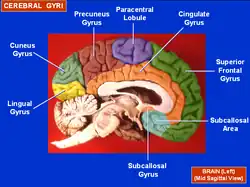

Medial surface of left cerebral hemisphere. (Precuneus visible at top left.) (Anterior to the right.) | |

In neuroanatomy, the precuneus is the portion of the superior parietal lobule on the medial surface of each brain hemisphere. It is located in front of the cuneus (the upper portion of the occipital lobe). The precuneus is bounded in front by the marginal branch of the cingulate sulcus, at the rear by the parieto-occipital sulcus, and underneath by the subparietal sulcus. It is involved with episodic memory, visuospatial processing, reflections upon self, and aspects of consciousness.

The precuneus is located on the inside between the two cerebral hemispheres in the rear region between the somatosensory cortex and forward of the cuneus (which contains the visual cortex). It is above the posterior cingulate. Following Korbinian Brodmann it has traditionally been considered a homogeneous structure and with limited distinction between it and the neighboring posterior cingulate area. Brodmann mapped it as the medial continuation of lateral parietal area 7.

Precuneus of left cerebral hemisphere (shown in red).

Precuneus of left cerebral hemisphere (shown in red). Medial surface of left cerebral hemisphere. (Precuneus visible at top left.)

Medial surface of left cerebral hemisphere. (Precuneus visible at top left.) Medial surface of left cerebral hemisphere. (Precuneus colored in red.)